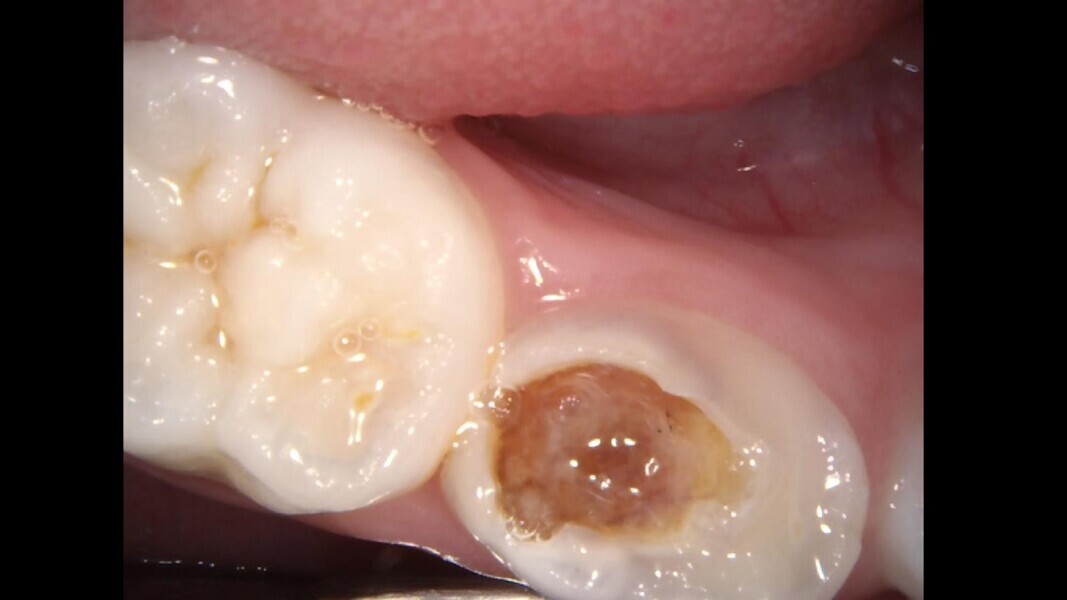

Case 3 (Figs. 10–13)

This male patient was 7 years old and presented with mild pain that had lasted for several days. An extensive and deep cavity in the mandibular left first primary molar was observed. There was no swelling of the gingiva, but the tooth was painful on percussion. The radiograph showed the severity of the decay but no consistent changes to the surrounding bone. Pulpectomy was the treatment of choice. The diagnosis of pulp necrosis was confirmed once the access cavity had been performed, and three canals were located and fully negotiated. At a second appointment, 15 days later, the tooth was totally asymptomatic and the decision was made to restore with a stainless-steel crown. The 36-month control showed the tooth to be in normal function and completely healthy.